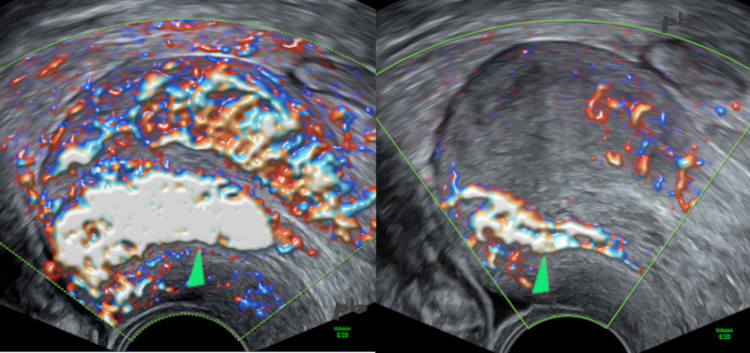

Echographie doppler – Coupes sagittales.

Grossesse arrêtée depuis 6 semaines.

Présence de flux nombreux et très rapides (►) en postérieur (utérus rétroversé).

Intérêt du réglage de la PRF en doppler couleur :

-image gauche : PRF basse visualisant tous les flux, lents et rapides, dans tout l’utérus.

-image droite : PRF élevée ne laissant persister que les flux rapides. Ils indiquent préférentiellement la présence de résidus trophoblastiques et la zone d’implantation.

Aspiration le même jour. Débris placentaires bordés par du cytotrophoblaste en anapath.